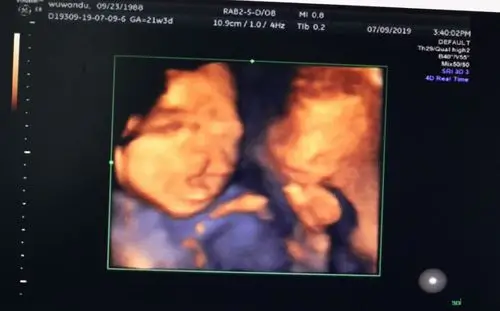

全前脑并单鼻孔)▼(胎儿唇裂)▼(部分案例)以下是通过我院美国ge-e8

【超声笔记】no.35 胎儿头颈五官畸形

避免胎儿畸形,产前超声检查是关键!

无叶型前脑无裂畸形(简称无叶全前脑),严重脑膜脑膨出等9种(2022年版

无叶型全前脑:脑中线消失,丘脑完全融合, 半叶型全前脑:脑中线部分